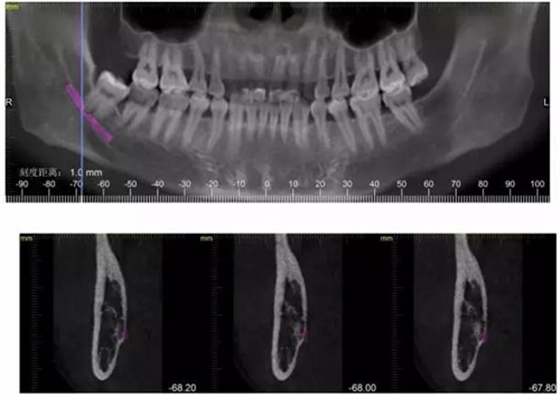

CBCT神經(jīng)管標(biāo)線,可以看到標(biāo)線不能連續(xù),中間被阻斷。

下面CBCT,可以看到兩個牙根的根尖三分之一在神經(jīng)管里面。